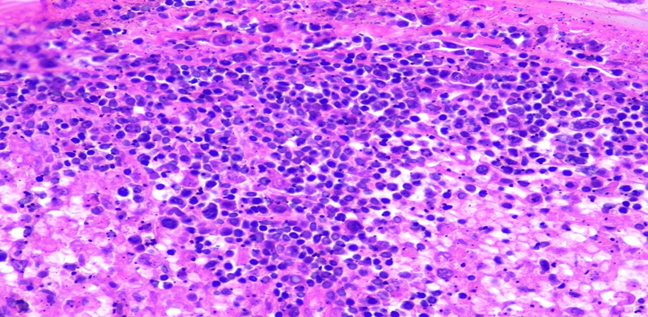

Figure 5C: Photomicrographs showing hemophagocytosis by macrophages in spleen (H&E, 40X magnification).

Spleen: Tissue architecture and cellular morphology showing many hemophagocytic cells highlighted with CD68 and CD163.

Respiratory System: Sections of the right and left lungs show variable areas of vascular congestion, emphysematous changes, intraalveolar edema, and interstitial stromal acute and chronic and inflammation with focal interstitial fibrosis. Pleural fibrin adhesion and subpleural acute and chronic inflammation are identified. Clusters of intravascular histotypes identified, highlighted with CD68 and CD163. Granulomas, fungal forms, viral cytopathic effects, dysplasia, and malignancy are not seen. Special stains of GMS, GRAM, PAS and Iron support the findings. (Figures 4, 5A-C, 6A-D, 7A-C).